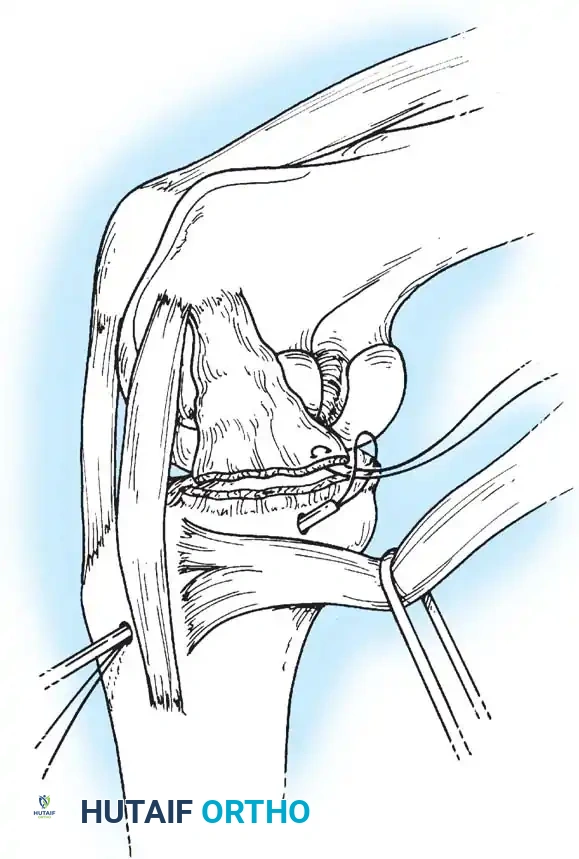

A curvilinear incision is made over the lateral aspect of the knee, incorporating the iliotibial band and the biceps femoris. The common peroneal nerve must be identified, neurolysed, and protected with a vessel loop throughout the procedure.

Image

The LCL, popliteus tendon, and popliteofibular ligament are systematically evaluated. Avulsions from the fibular head are common.

Deep capsular tears are repaired with interrupted sutures. If the LCL or popliteus is avulsed from the lateral femoral epicondyle, anatomical footprints are identified, and the structures are repaired using suture anchors. Tensioning must be performed with the knee in 30 degrees of flexion and neutral rotation.